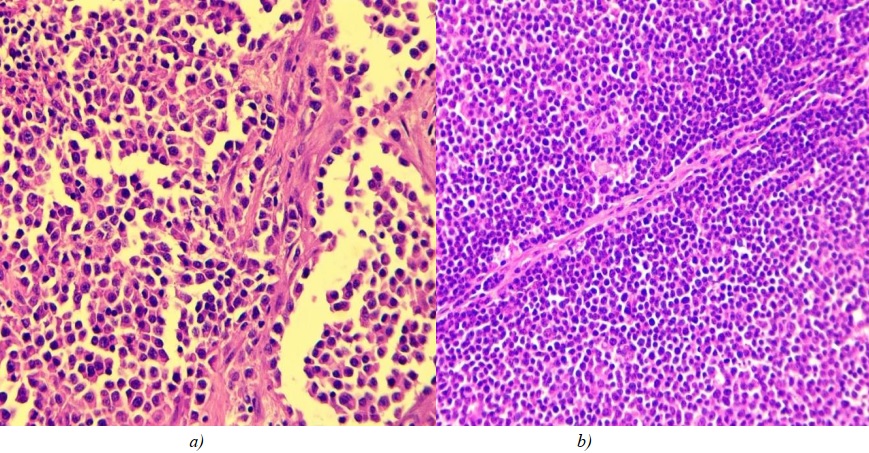

Large-cell tumours had large, eccentrically arranged nuclei. The condensed chromatin structure resulted in nucleoli being differentiated within the nuclei (Fig. 1). At 400x magnification, 5 to 10 mitoses were detected per field of view.

Fig. 1. a — large-cell nodal lymphoma; b — fibrous tissue strand in the center of tumour.

Hematoxylin and eosin staining, ×400 magnification

All large cell nodal lymphomas showed thin fibrous septa, which constitute the tumour stroma. These septa are likely to be the residues of the interfollicular septa of a lymph node (Fig. 1 b).